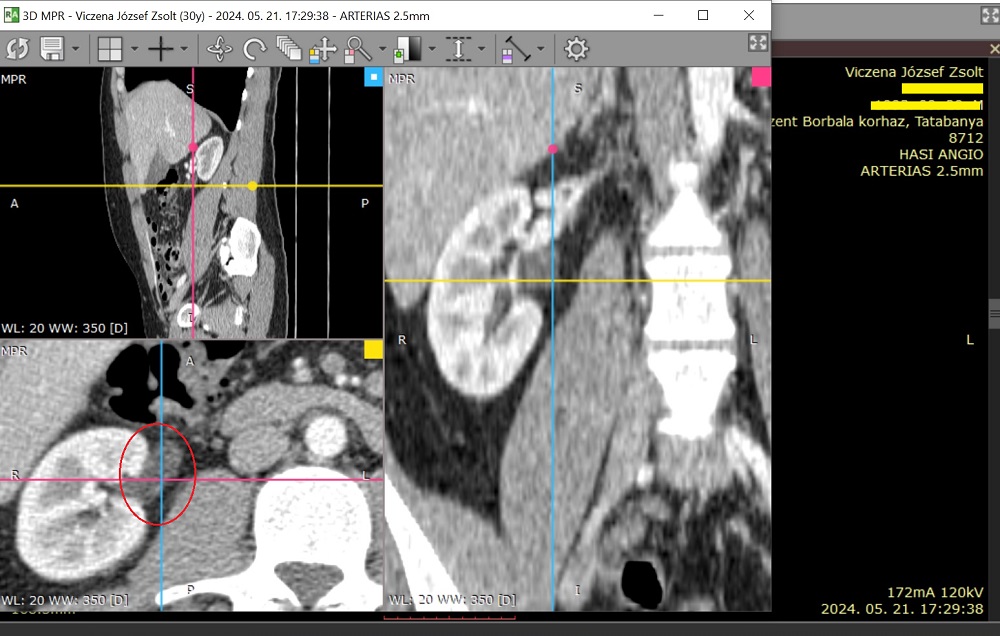

Súlyos kétoldali vesefájdalommal érkezett a fiam, aki túlélte a szeptikus állapotot, amivel itt volt először. Erre következetesen bal veséről írtak a felvételkor és a CT leletben. Merthogy történt egy CT Angiográfia. A vesemedencék (pyelonok) extrarenális helyzetűek – írta a távleletező viszonylag kezdő radiológus. A tatabányai kórházban ezt nem beszélték meg szakemberrel. Ami azért lett volna kulcsfontosságú, mert Zsoltnál azok nem veleszületetten voltak ilyenek, ahogy gondolták, hanem a fertőzés ideje alatt keletkeztek, akkor „csúsztak ki helyükről a vesén kívülről, nem is kicsit!” Ugyanezt igazolta az 1 hónappal korábbi MR urográfia is. Gyakorlatilag negatív leletet adtak ki, és a fiamat hazaküldték, miközben a veséi kiszakadtak a fájdalomtól és a neuropátiától (Cipro) úgy égett a teste, hogy az szavakkal nem fejezhető ki, elképesztő erő kellett, hogy kitartson. Mivel a fiamnak az addigra már 10 éve tartó betegsége alatt több tucat CT, CTA, MR, MRA és más képalkotó készült, pontosan visszanézhető milyenek voltak a veséi, milyen anatómiájúak, milyen vesékkel született – és hát nem extrarenális pyelonokkal. Teljesen normális anatómiájú, sosem fájó veséi voltak. Talán úgy mondanák szakmailag, intrarenalis pyelonjai voltak, a vesén belüli helyükön, ahogy kell. A vesén kívülre került vesemedencék a súlyos, közel 4 hónapja tartó kezeletlen vesemedence-gyulladás következményeként „csúsztak ki”. És lehet, hogy feszítik a magukkal „húzott” szöveteket, idegeket és ezért veszik meg a fiam a fájdalomtól!

Alább a 2024.05.21-én készült CTA egy képe a vesékről, vesemedencéről:

Érdemes megnézni az alábbi képet is – Hiába készítettük el Zsolt förtelmes kezeletlen állapotában is precízen, magánúton április 16-án az MR Urográfia vizsgálatot Veszprémben, az eredményeket már senki nem vetette össze, nem konzultálta meg, nem foglalkozott vele. Az alábbi képeket a fiam mentette ki a CT-ből és MR-ből. De ő azt mondja, a fenti kép szerinte jobban mutatja, milyen mértékben jött ki a helyéről a vesemedence!

Összefoglalva: a felvétel olyat mutat, amit korábban a kb húsz CT és MR felvétele soha. A vesemedencék kicsúsztak a veséből, extrarenálisak lettek a kezeletlen fertőzés miatt. Tehát nem veleszületetten „ampulláris tipusúak” – mint ahogy azt a veszprémi leletben írták (legyen mentségükre, hogy nem volt összehasonlító felvétel náluk). És lehet, hogy ez okozza az elviselhetetlen, kétoldali „kirepedő” érzést kiváltó vesefájdalmat? A háziorvos szerint, aki korábban sebész volt, lehet, hogy a korábban gyulladt, megduzzadt vesemedencék kicsúszva a veséből húzzák a vesetokot? Ezt kellene radiológusnak, urológusnak együtt kivizsgálni, hogy végre kiderüljön az embertelen vesefájdalom oka. Lehet, hogy ez eljuttathat a megoldáshoz, a fiam szenvedésének megszűnéséhez.